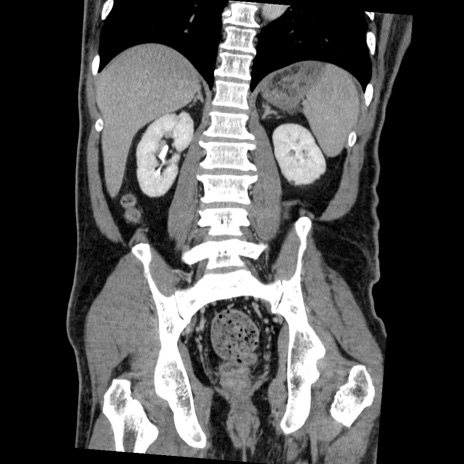

症例22(冠状断像)

【症例】50歳代男性

【主訴】腹痛

【現病歴】AVMからの被殻出血のため回復期リハ病棟入院中。 本日午後3時頃急に下腹部痛が出現した。

【既往歴】AVM、被殻出血、虫垂炎、高血圧

【身体所見】意識晴明、左半身不全麻痺、会話の理解は良好、36.5°C、腹部:膨隆、全体に板状硬、下腹部正中に圧痛点あり、反跳痛-、筋性防御不明、右下腹部にope scar

【データ】WBC 9400、CRP 0.06